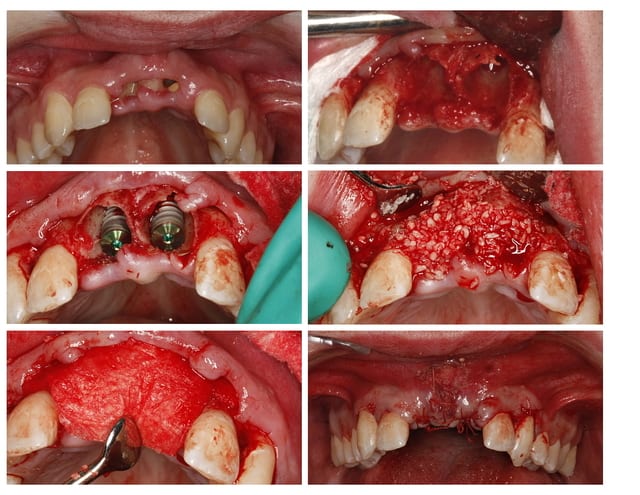

Situation semblable.

Jeune homme, 20 ans, accident de vélo.

Perte de 11 et 21.

Arrive dans mon cabinet 8 jours post trauma.

J'ai placer sous antibio et 2 jours après j'ai curetté les alvéoles, fait lambeau (perte de paroie buccale), placer 2 4,6 X 15 mm en palatin, greffe MINEROS, membranne (suturée sous le lambeau palatin + 2 tacs en titane au buccal).

Extension du lambeau au buccal et fermeture.

Ah oui, freinectomie laser en mêm temps, histoire de s'occuper un peu. Pas de temporisation sur implants avec une perte d'os au buccal. Prothèse acrylique amovible de transition, placée 7 jours post-op.

La 2e photo est 7 jours post-op, la sem dernière.

Zéro enflure, zéro douleur, pas d'anelgésique.